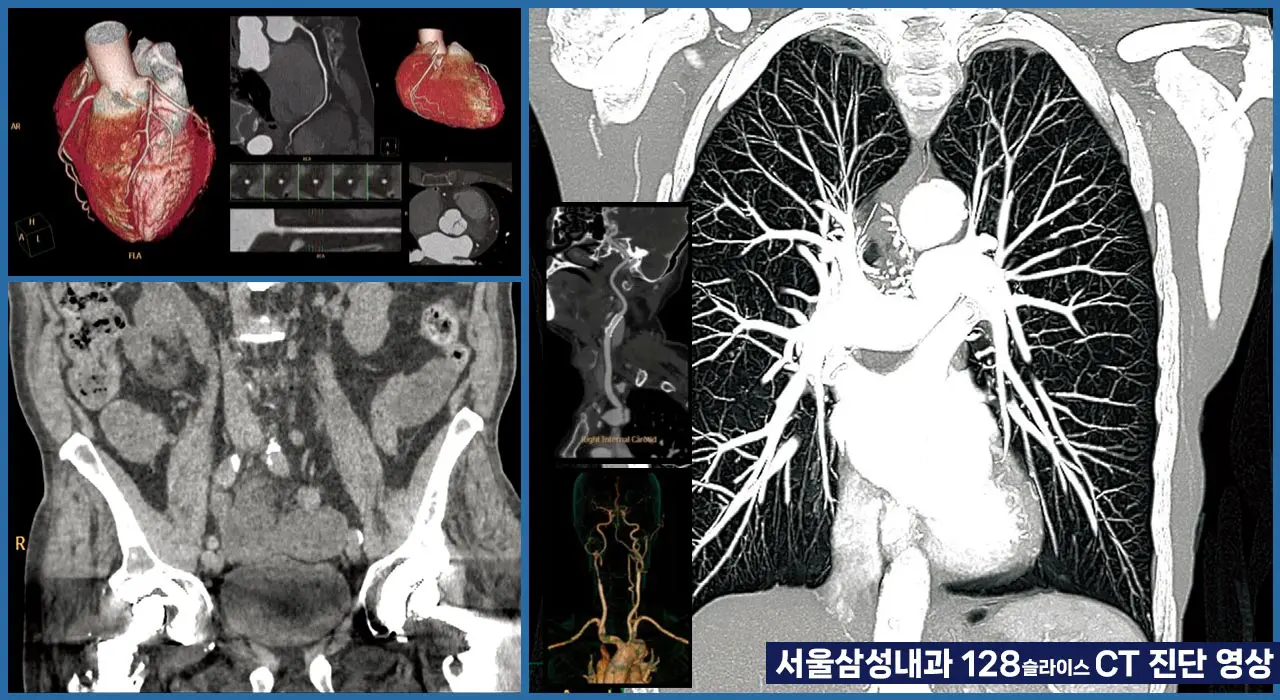

- 저선량 흉부CT

- 조기 폐암 환자의 대부분은 검진에서 시행되는 저선량 흉부CT에서 발견되지만, 국민건강검진 시행도 얼마되지 않았고, 54~74세 고위험군에 한해 격년제로 시행되고 있어 발견 비율은 아쉽게도 10% 내외에 불과합니다.

- 저선령CT의 장점

- 방사선 노출 감소로 비교적 안전하여 고위험군 진단에 매우 유용합니다. 유전적 요인이 있거나, 흡연자, 장기간 간접흡연 노출자, 작업환경의 공기질이 좋지 않을 경우 적극적인 상담을 통해 정기적인 저선량 폐CT가 필요할 수 있습니다.